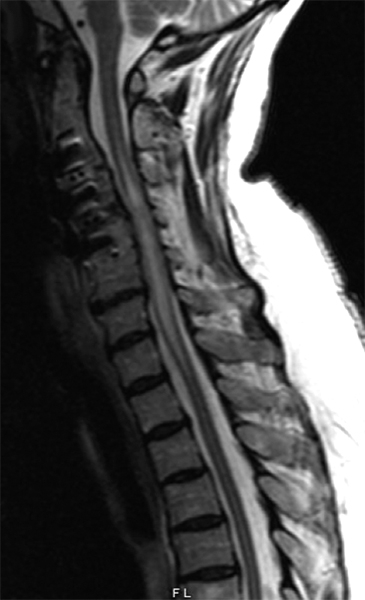

Q7: A 75-year-old woman with history of prior cervical spine decompression presented with progressive neck pain, asymmetric hand tingling, and neuropathic pain, followed by urinary incontinence and gait difficulty. Sagittal T2 weighted imaging likely shows?.